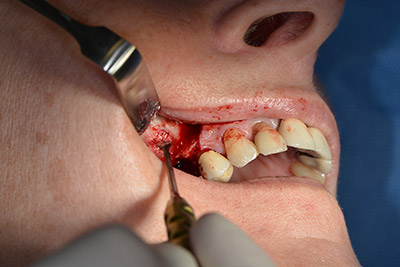

Класическият разрез (крестално, букално освобождаване) и подготовката на мукопериостално ламбо осигуряват добра видимост.

Импланти Sky (Bredent) са използвани в този случай. Хирургичният протокол за тях изисква пилотно пробиване с дрил при 1200  rpm  (Фиг. 9).

Последващите отвори се изборват с намалени обороти от 300 rpm. Implantmed демонстрира своя истински потенциал на този етап. Хирургичният протокол може да бъде зададен – различните позиции могат да бъдат лесно избрани чрез натискане на позиция “P” на педала (Фиг. 10 и 11).